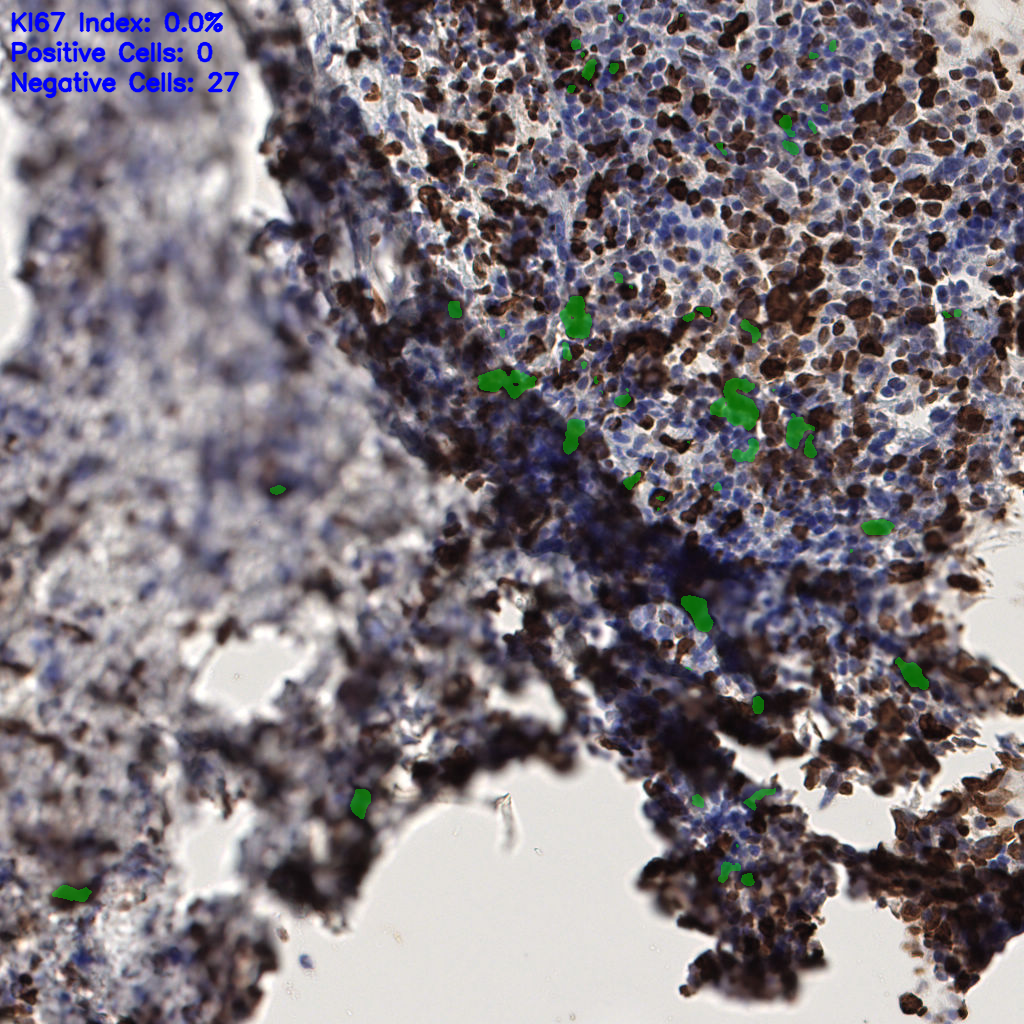

Ki67 指数

阴 1104

阳 94